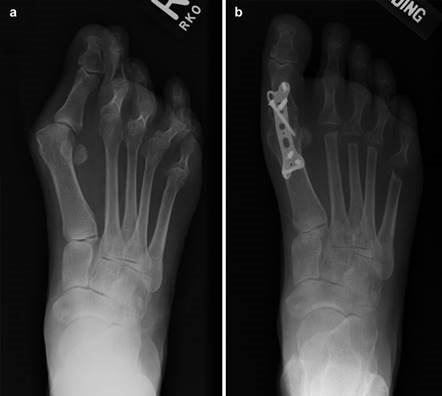

A V-shaped osteotomy is then created in the metatarsal neck with an apex angle of approximately 60 degrees. The apex is positioned centrally within the metatarsal head, and the limbs exit dorsally and plantarly. The capital fragment is translated laterally by 30-50% of the metatarsal shaft width. If the DMAA is increased, a medial closing wedge can be incorporated into the osteotomy. The osteotomy is provisionally stabilized with a Kirschner wire, and definitive fixation is achieved using one or two headless compression screws directed from dorsal-proximal to plantar-distal. The medial capsule is then imbricated to correct the soft-tissue imbalance, and the skin is closed in layers.

To achieve multiplanar correction, the surgeon must address the sagittal, coronal, and transverse planes. The first metatarsal is plantarflexed to restore the longitudinal arch, rotated out of pronation to realign the sesamoids, and translated laterally to close the IMA. Subchondral drilling or feathering is performed to optimize the biological environment for fusion. Fixation is traditionally achieved with two or three crossed solid or cannulated screws (typically 3.5mm or 4.0mm). Recently, plantar or medial locking plates have gained immense popularity due to their superior biomechanical construct, allowing for earlier weight-bearing. Bone graft or orthobiologics may be packed into the arthrodesis site to stimulate osteogenesis.

Clinical & Radiographic Imaging Archive